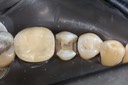

Kyle Chock #14 finish